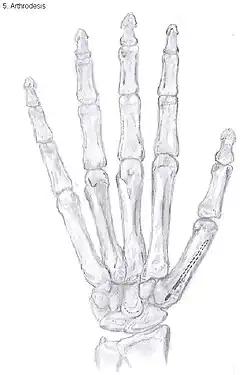

Showing the bones of the hand

Arthrodesis of the thumb

Arthrodesis

Arthrodesis of the TMC joint is a surgical procedure in which the trapezium bone and the metacarpal bone of the thumb are secured together. They are held together by K-wires or a plate and screws until the bone will heal.

Disadvantages include inability to flatten the hand.[27] Additionally, the stress on the CMC joint is now spread over the adjacent joints, those joints are more likely to develop osteoarthritis.[34]

Nevertheless, this procedure can be used in patients with stage II and III CMC OA as well as in young people with posttraumatic osteoarthritis.[27]